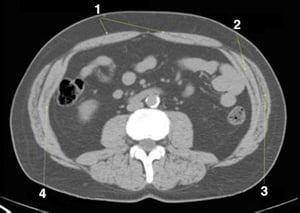

CT-Scan von Abdomen und Becken mit normaler Anatomie ohne Kontrastmittel (Folie 19)

1 = M. rectus abdominis; 2 = M. obliquus internus abdominis; 3 = M. obliquus externus abdominis; 4 = M. transversus abdominis.

1 = M. rectus abdominis; 2 = M. obliquus internus abdominis; 3 = M. obliquus externus abdominis; 4 = M. transversus abd

© Springer Science+Business Media